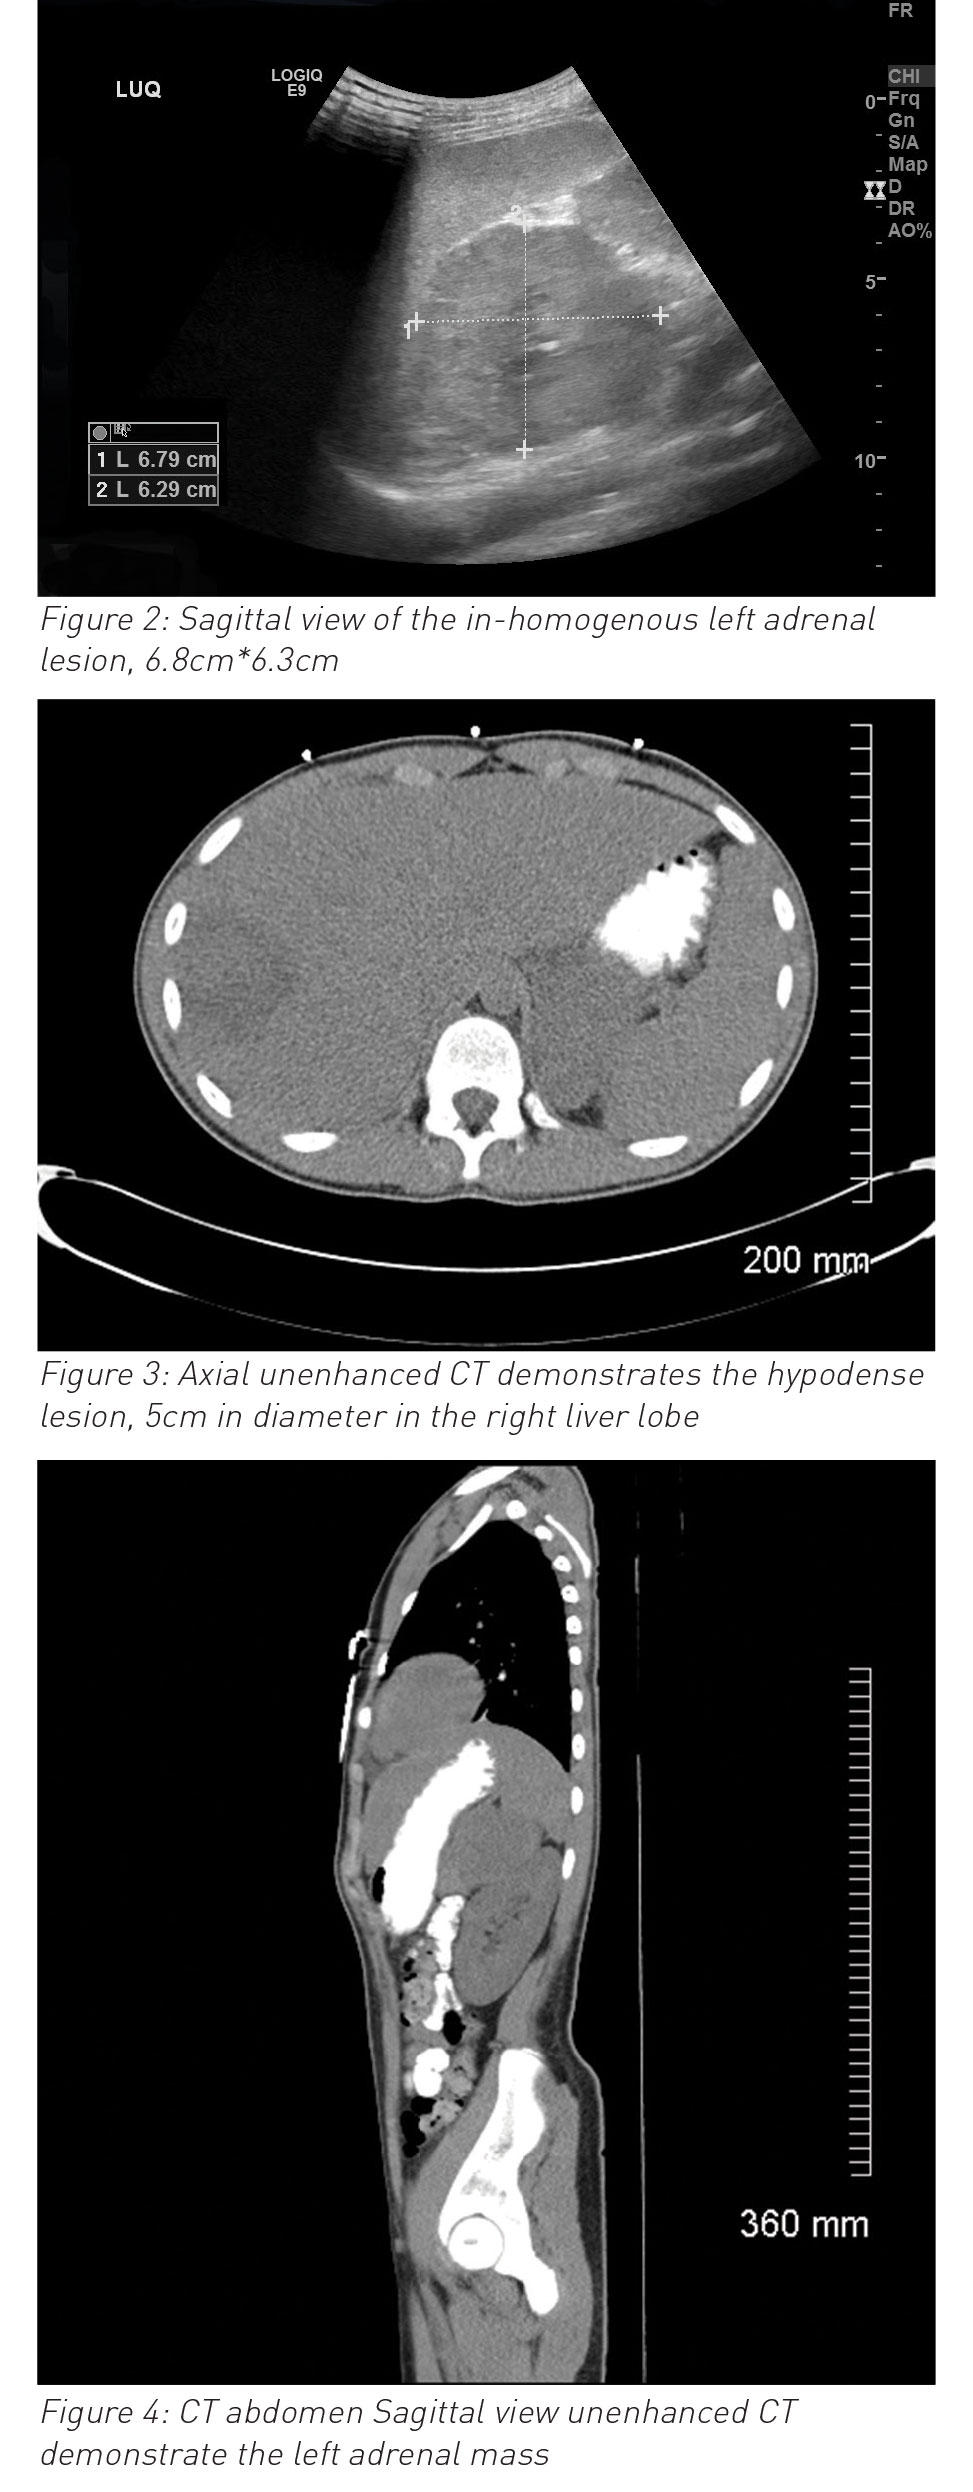

During his hospital stay it was noted that he had an episode of high blood pressure (140/90mmHg) and developed ventricular bigeminy and trigeminy (see ECG in Figure 1). Chest x-ray and echocardiography were normal. Ultrasound and MRI abdomen reported left side suprarenal mass (8cm) and associated liver abscess (7cm x 7cm x 7cm). Urine catecholamines were normal. Liver abscess (abscess grew Streptococcus intermedia) was treated with drainage and with six weeks antibiotics. Paraganglioma was surgically resected successfully three months after initial diagnosis and full evaluation (genetic testing and exclusion of MEN syndrome and von-Hipple-Lindau syndrome). Ventricular bigeminy resolved completely and final diagnosis of non-secreting pheochromocytoma and coincidental liver abscess (likely due to trauma in the past). He was discharged home after full recovery. He is being followed up with regular abdominal imaging; to date, no concerns have been reported.